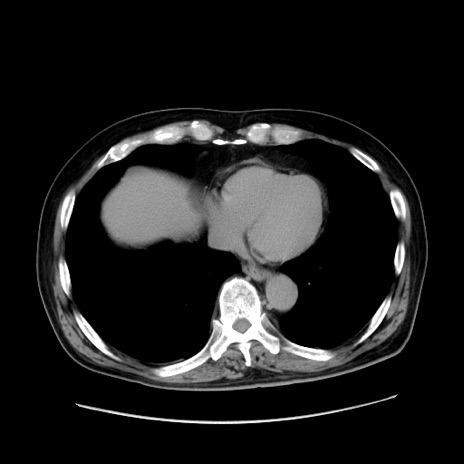

冠状断像

【症例】80歳代男性

【現病歴】約6時間前から臍下部痛が出現。次第に腹部膨隆・背部痛も生じてきたため来院。背部痛の場所は変化しない。

【身体所見】意識清明、BT 36.3℃、BP  131/87mmHg、P 87bpm、SpO2 100%(RA)、臍周囲自発痛・圧痛あり、反跳痛なし、自発痛部位に一致して板状硬あり、腹部膨隆、腸雑音減弱、CVA tenderness両側陰性。